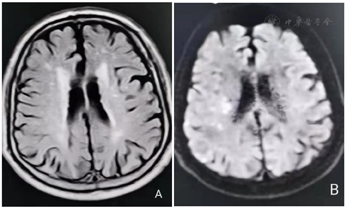

颅脑MRI示双侧侧脑室旁、右侧基底节区及脑干多发梗死灶。

颅脑MRI+DWI结果,见图1。

临床诊断:①脑梗死恢复期(右侧大脑中动脉供血区动脉粥样硬化性);②脑梗死后遗症(脑干及双侧侧脑室旁);③高血压病3级(很高危)。